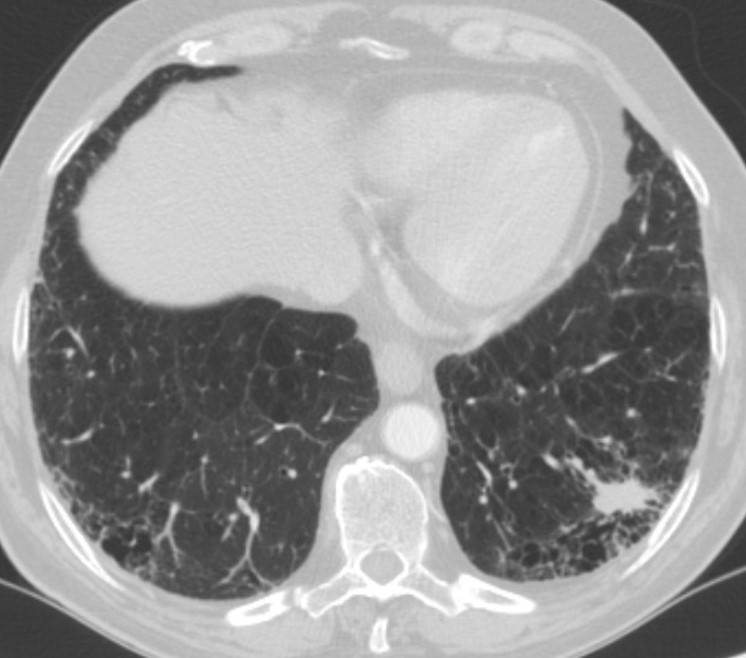

Patient's computed tomography scan.

This video shows a posterobasal (S9+10) left lower lobe segmentectomy for a lepidic adenocarcinoma of 1.7 cm without nodal involvement. Arterial segmental division can be easily achieved when the pulmonary artery is divided by identifying the central branch of the artery (between the upper segment artery A6 and the anterior segment artery A8). Division of the vein requires careful identification of segmental veins for the upper segment, anterior segment, and posterobasal segments. There is a high frequency of variation in the intersegmental veins, so special attention should be focused to clearly determine which of the veins drains S9+10 in order to preserve venous drainage for the remaining segments and avoid segmental infarction [4].